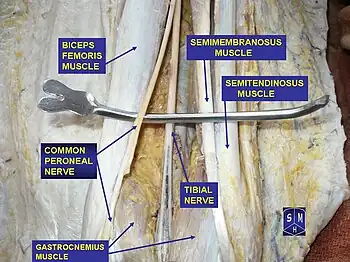

In humans, the sciatic nerve is formed from the L4 to S3 segments of the sacral plexus, a collection of nerve fibres that emerge from the sacral part of the spinal cord. The lumbosacral trunk from the L4 and L5 roots descends between the sacral promontory and ala and the S1 to S3 roots emerge from the ventral sacral foramina. These nerve roots unite to form a single nerve in front of the piriformis muscle. The nerve passes beneath piriformis and through the greater sciatic foramen, exiting the pelvis.[1]: 422–4 From here, it travels down the posterior thigh to the popliteal fossa. The nerve travels in the posterior compartment of the thigh behind (superficial to) the adductor magnus muscle, and is itself in front of (deep to) the long head of the biceps femoris muscle. At the popliteal fossa, the nerve divides into its two branches:[1]: 532

- The tibial nerve, which travels down the posterior compartment of the leg into the foot

- The common fibular nerve (also called the common peroneal nerve), which travels down the anterior and lateral compartments of the leg into the foot

The sciatic nerve supplies sensation to the skin of the foot, as well as the entire lower leg (except for its inner side). Sensation to skin to the sole of the foot is provided by the tibial nerve, and the lower leg and upper surface of the foot via the common fibular nerve.[1]: 422–4

The sciatic nerve also innervates muscles. In particular:[1]: 422–4

- Via the tibial nerve, the muscles in the posterior compartment of the leg and sole of the foot (plantar aspect).[lower-alpha 1]

- Via the common fibular nerve, the muscles in the anterior and lateral compartments of the leg.[lower-alpha 2]

Structures surrounding left hip-joint. Nerves of the right lower extremity. Posterior view.